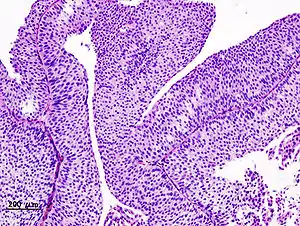

Papillary transitional cell carcinoma, low grade

Micrograph of urethral urothelial cell carcinoma. Hematoxylin and eosin stain.